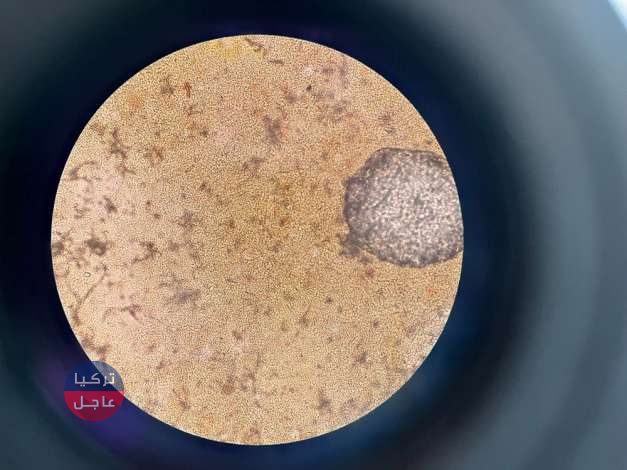

أظهرت الأشعة السينية، التي شاركها طبيب على تويتر، مئات النقاط المضيئة، كل منها يمثل البقايا المستقرة لطفيلي.

تحدث الحالة، التي تسمى داء الكيسات المذنبة، عندما تدخل يرقات نوع من الدودة الشريطية تعيش عادة في الأمعاء إلى الأنسجة مثل العضلات أو الدماغ.

يصاب الناس بهذه الديدان الشريطية عن طريق تناول الطعام الملوث عن طريق الخطأ، وخاصة اللحوم والفاكهة غير المغسولة والمشروبات، وتشكل اليرقات كتل صلبة على شكل أكياس يمكن الشعور بها من خلال الجلد.

ومع ذلك، تعتبر الحالة غير ضارة بشكل عام، حيث تموت الديدان الشريطية بسرعة، ومع ذلك، فإن الأكياس التي خلفتها الديدان الشريطية الميتة يمكن أن تسبب مشاكل صحية يمكن أن تؤدي إلى الوفاة. ويحدث السعال وألم الصدر عندما تلتصق الأكياس برئتيك.